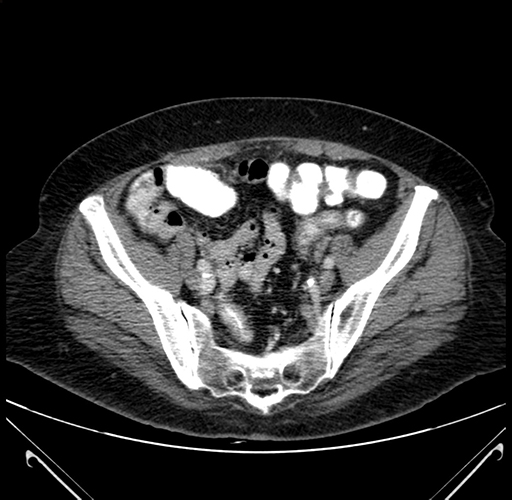

Axial Venous